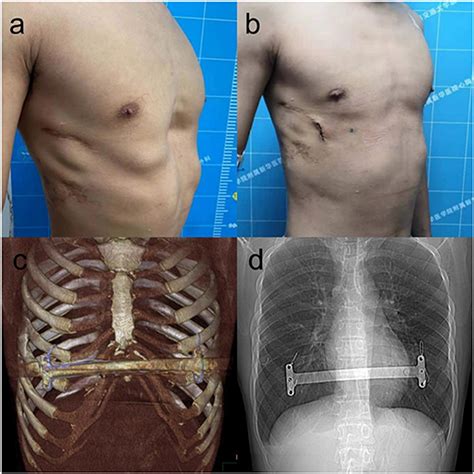

Modified Nuss Procedure for Recurrent Pectus Excavatum After Ravitch: A Case Study